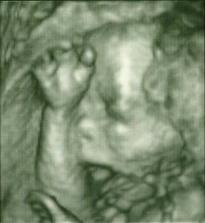

Naše druhé :o)